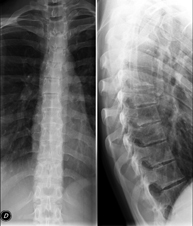

- RX Columna dorsal

Técnica mediante la cual, utilizando rayos X, se obtienen imágenes de la columna dorsal para su estudio. Indicaciones: traumatismo, dolor de espalda.

- RX Columna lumbar

Técnica mediante la cual, utilizando rayos X, se obtienen imágenes de la columna lumbar para su estudio. Indicaciones: ciática, traumatismo, dolor lumbar.

- Telerradiología columna

Técnica mediante la cual, utilizando rayos X, se obtienen imágenes de toda la columna vertebral para su estudio, valorando especialmente la presencia de escoliosis y dismetrías pélvicas.